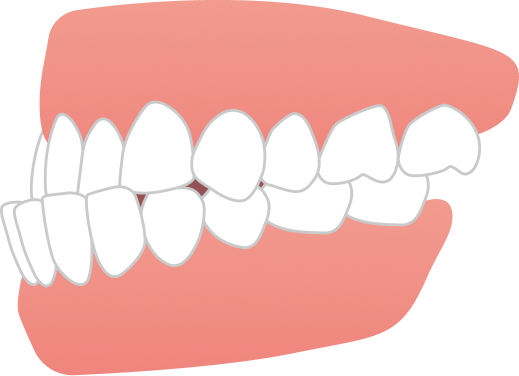

治療後は

・前歯でしっかり噛める噛み合わせ

・横顔の印象が整った美しい口元

AFTER

| 施術内容 | 歯全体のマウスピース矯正システム「インビザラインアドバンス」を用いた治療 |

| 治療期間 | 2年8ヶ月 |

| 費用 | 1,034,000円(税込) |